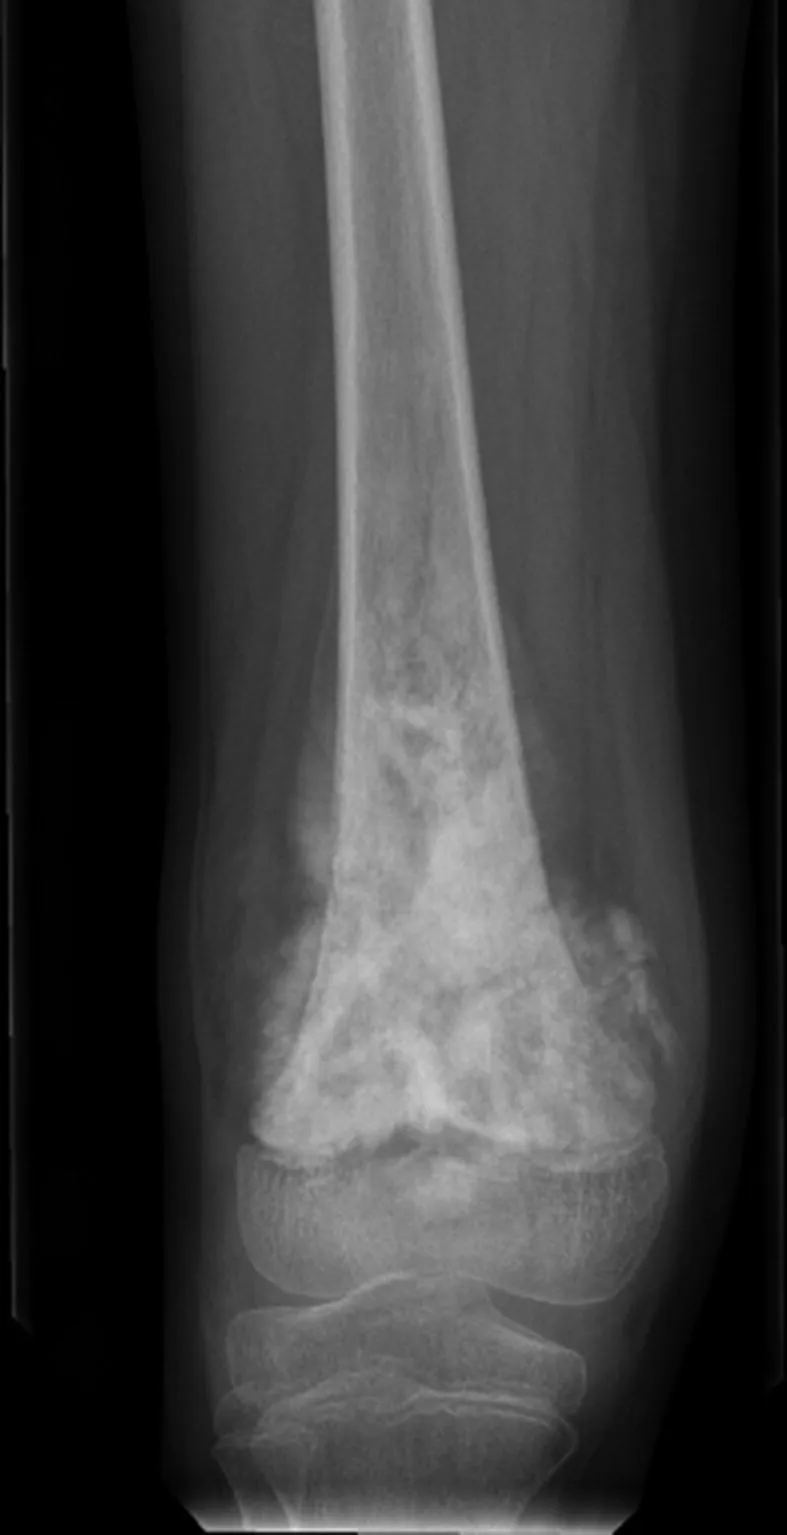

⭐ The classic X-ray findings are a "sunburst" pattern and Codman's triangle.

- X-Ray Findings (Classic Triad):

- Sunburst appearance: Spiculated periosteal reaction.

- Codman's triangle: Triangular elevation of the periosteum.

- Destructive, ill-defined mixed lytic & sclerotic lesion.

- Classic X-ray findings include Codman's triangle and a "sunburst" pattern.